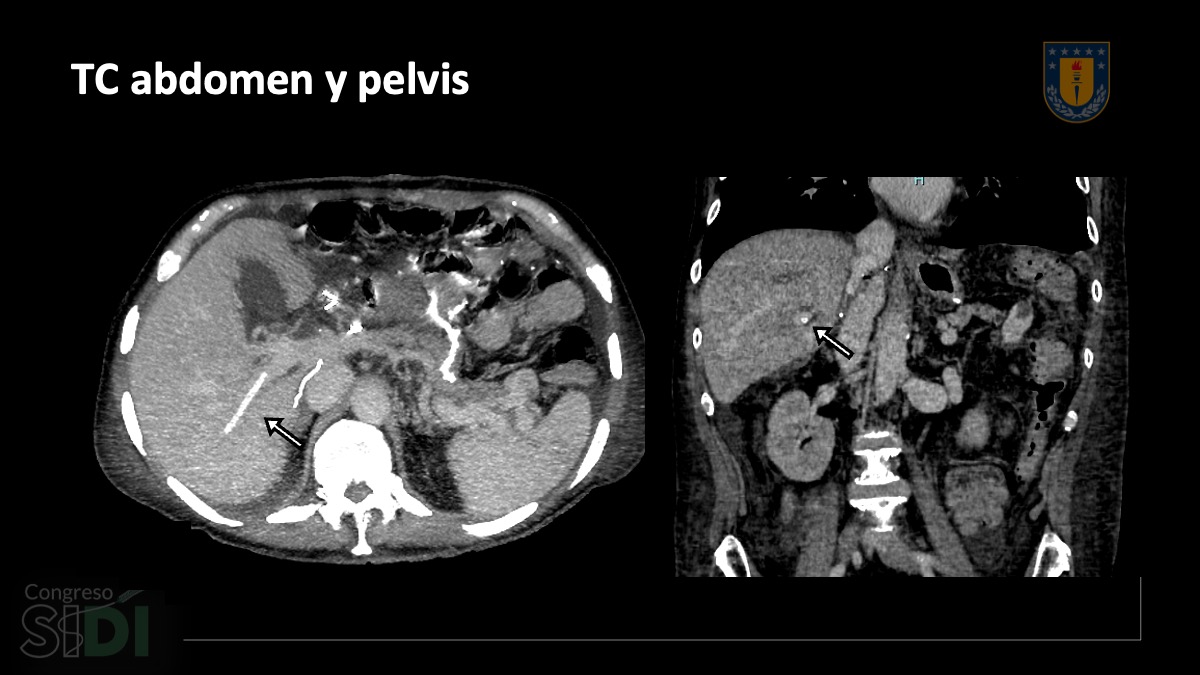

SIDI25_PE_014_Cristian Lindner_04